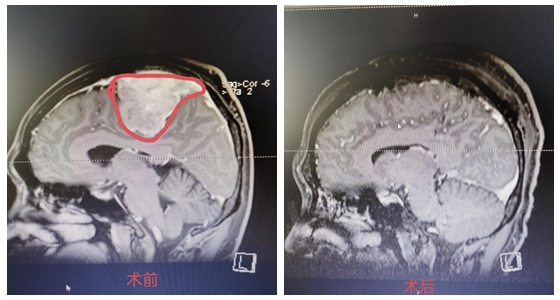

近日,湘雅常德医院神经外科团队成功为来自山东的王女士切除6*5.5*5.2cm大小的巨大岩斜坡区脑膜瘤。     年仅40多岁的王女士因头晕、左侧听力下降,检查出脑肿瘤10年余,一...